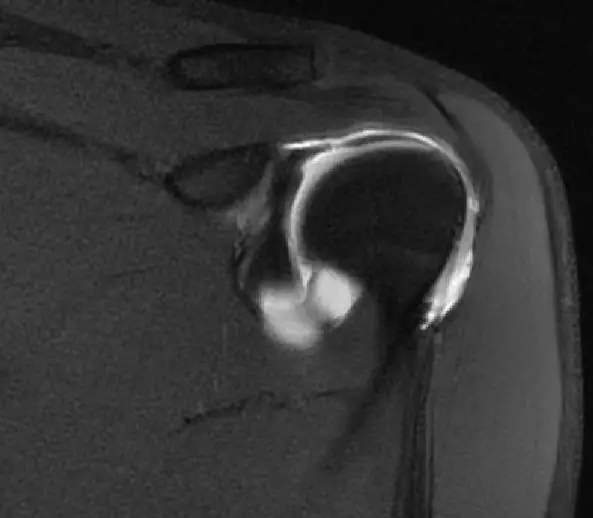

这张片子是肩胛下肌,上盂唇,冈上肌,冈下肌

到这个层面,可以看到肩胛下肌建,冈上肌腱,冈下肌建